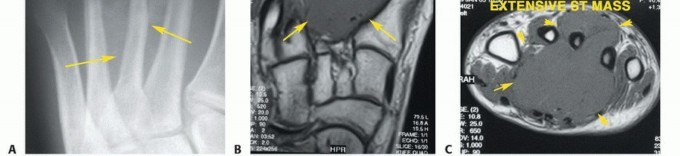

- الأشعة السينية (X-rays): هي الخطوة الأولى لتحديد ما إذا كان الورم عظميًا، وتقييم حجمه، وشكله، ومدى تأثيره على بنية العظم.

- التصوير بالرنين المغناطيسي (MRI): يوفر صورًا مفصلة للغاية للأنسجة الرخوة (العضلات، الأوتار، الأعصاب، الأوعية الدموية) والعظام، مما يساعد على تحديد مدى انتشار الورم بدقة، وعلاقته بالهياكل المحيطة. يعتبر التصوير بالرنين المغناطيسي ضروريًا لتخطيط الجراحة.

- التصوير المقطعي المحوسب (CT Scan): يستخدم لتقييم تفاصيل بنية العظام، خاصة في حالات الأورام العظمية، ويمكن استخدامه لتقييم انتشار الورم إلى الرئتين (في حالات الأورام الخبيثة).

- تُعد الخزعة هي الطريقة الوحيدة المؤكدة لتحديد طبيعة الورم (حميد أم خبيث) ونوعه الدقيق.

- يقوم الأستاذ الدكتور محمد هطيف بإجراء الخزعة بدقة عالية، غالبًا تحت توجيه الأشعة (مثل الأشعة المقطعية أو الموجات فوق الصوتية) لضمان أخذ عينة ممثلة من الورم.

- يمكن أن تكون الخزعة بالإبرة (Needle Biopsy) أو خزعة جراحية مفتوحة (Open Surgical Biopsy). يتم تحليل العينة بواسطة أخصائي علم الأمراض لتحديد التشخيص النسيجي.